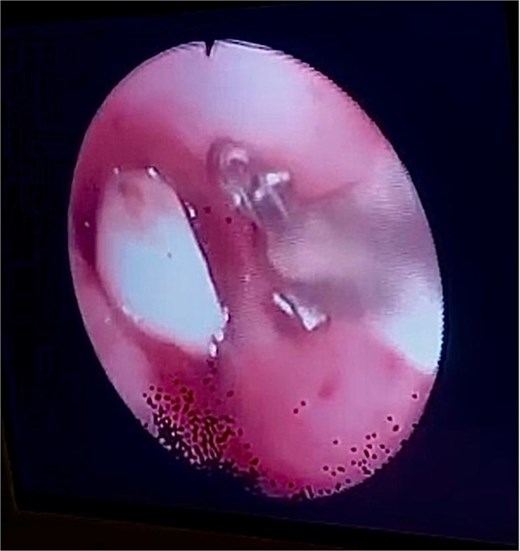

After obtaining informed and written consent, an emergency fiberoptic bronchoscopy was performed in the ICU on 20 October 2022. During the procedure, a FB was visualized at the origin of left mainstem bronchus. The decision was to extract the FB using endobronchial basket. However, the basket could not be deployed and opened in the left main bronchus due to the small size of the bronchus. To address this issue, the team utilized an endoscopic retrograde cholangiopancreatography (ERCP) balloon to mobilize the dental bridge from the left mainstem bronchus to the carina, facilitating the removal of the FB. Following that, the endobronchial basket was passed and opened to capture the dental bridge.

Bronchoscopy view showing the dental bridge lodged in the left mainstem bronchus.

Rigid bronchoscopy remains the preferred choice in emergencies requiring rapid FB removal [13]. While flexible bronchoscopy succeeded in this case, challenges like deploying the endobronchial basket in a small bronchus raise questions about its suitability. Rigid bronchoscopy is often more effective for quick removal [14]. FBs are commonly found in the right bronchial tree due to its anatomy [16]. However, in this case, the FB was lodged in the left mainstem bronchus. Using a flexible bronchoscope, the team mobilized the FB to the carina with an ERCP balloon, then extracted it using an endobronchial basket. The ERCP balloon’s innovative use highlights the adaptability of endoscopic techniques. However, its broader applicability needs further validation, as it requires specialized skills and equipment [17].